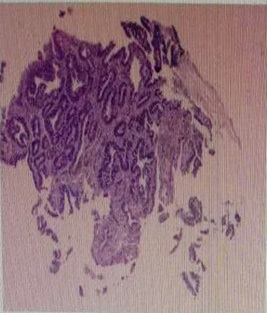

The patient, a 55-year-old male, was admitted to the hospital on March 11, 2021 due to “upper abdominal distension, pain and discomfort for more than 1 year, and recurrence for more than 2 months”. More than 1 year ago, the patient had no obvious inducement of upper abdominal distension, pain and discomfort, no acid reflux, heartburn, no nausea, vomiting, no hemesis, melena, no chest pain, chest tightness and other discomfort, no care, no diagnosis and treatment. Before 2 months, the patient’s symptoms were aggravated again, and the symptoms continued to be not relieved, so the emergency department was admitted to our hospital as “abdominal distension cause check”. Previous healthy, smoking and drinking history, no similar patients in the family. Improve relevant examinations after admission, such as: Infectious disease screening: hepatitis B surface antigen (gold standard method) positive (+), HBVDNA: 3.89 x 106 IU/ml, TAP: 128.03 um², liver function:TP: 50.23 g/L ALB: 27.8 g/L, TBIL: 34.8 g/L, DBIL: 15.00 g/L, IBIL: 19.8 g/L, ALT: 27 g/L, AST: 51 g/L, PCHE: 1879 g/L, AFP: 203.8 ng/ml, Color Doppler ultrasonography of chest and abdomen showed that liver cirrhosis was possible, portal vein velocity decreased, liver disease gallbladder, splenomegaly and splenic vein dilation. 256 row chest and upper abdomen CT (plain scan + enhanced): 1. Ground glass shadow of left lung, follow-up and reexamination are recommended; 2. Liver cirrhosis, splenomegaly, esophagogastric fundus and splenic collateral circulation; The abnormal enhancement focus in the right lobe of the liver, considering the high possibility of liver cancer, the remaining small nodule like enhancement in the liver, considering intrahepatic metastasis (Figure 1). 3. Gastric antrum space occupying, considering malignancy, please combine clinical and pathological findings. 3.0 Mr upper abdomen (plain scan + enhancement): 1. Liver cirrhosis with regenerative nodules, splenomegaly, portal hypertension, ascites and collateral circulation; 2. Abnormal signal of right posterior lobe of liver (Figure 2). Considering malignancy, please combine clinical and AFP examination. Gastroscopy showed: 1. Esophageal gastric fundus varices (severe); 2. Gastric antrum space occupying: Ca? (Figure 3); Gastric antrum pathology (HE staining Figure 4) results: (gastric antrum) adenocarcinoma. Liver puncture pathology (immunohistochemical (Figure 5) diagnosis: (liver puncture) combined with immunohistochemical results, it is consistent with hepatocellular carcinoma. Immunohistochemistry: CerbB2 (0), CK (+), HEPA (partial +), glypican (+), CD (small amount +), CD34 (blood sinus +), CK7 (-), CK8 (+), CK19 (-), CDX2 (-), Ki67 (50% +), GS (+), CK20 (-). Physical examination: Body temperature was 37OC, pulse was 78 beats/ min, respiration was 20 beats/min, blood pressure was 120/70 MHg, skin and mucosa of the whole body were mildly yellow, no rash, bleeding spots, liver palm or spider nevus, superficial lymph nodes were not touched and enlarged, and no obvious abnormalities were found in head, neck, heart and lungs during physical examination. Abdominal distention, soft abdomen, no obvious tenderness, rebound pain and muscle tension in the abdomen, liver, spleen and ribs are not touched, negative mobility dullness, bowel sounds are normal. The patient refused interventional therapy, asked for oral chemotherapy and was discharged after her symptoms improved.

Figure 4: Antrum biopsy of the patient under gastroscopy for pathological examination of fruit (hematoxylin-eosin (HE) staining, ×100).